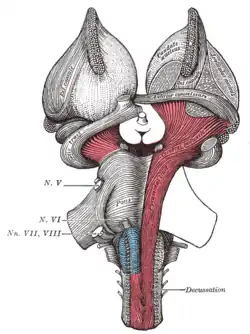

Deep dissection of brain-stem. Lateral view. ("pyramidal tract" visible in red, and "pyramidal decussation" labeled at lower right.) | |

Dissection of brain-stem. Lateral view.

Dissection of brain-stem. Lateral view. Superficial dissection of brain-stem. Ventral view.